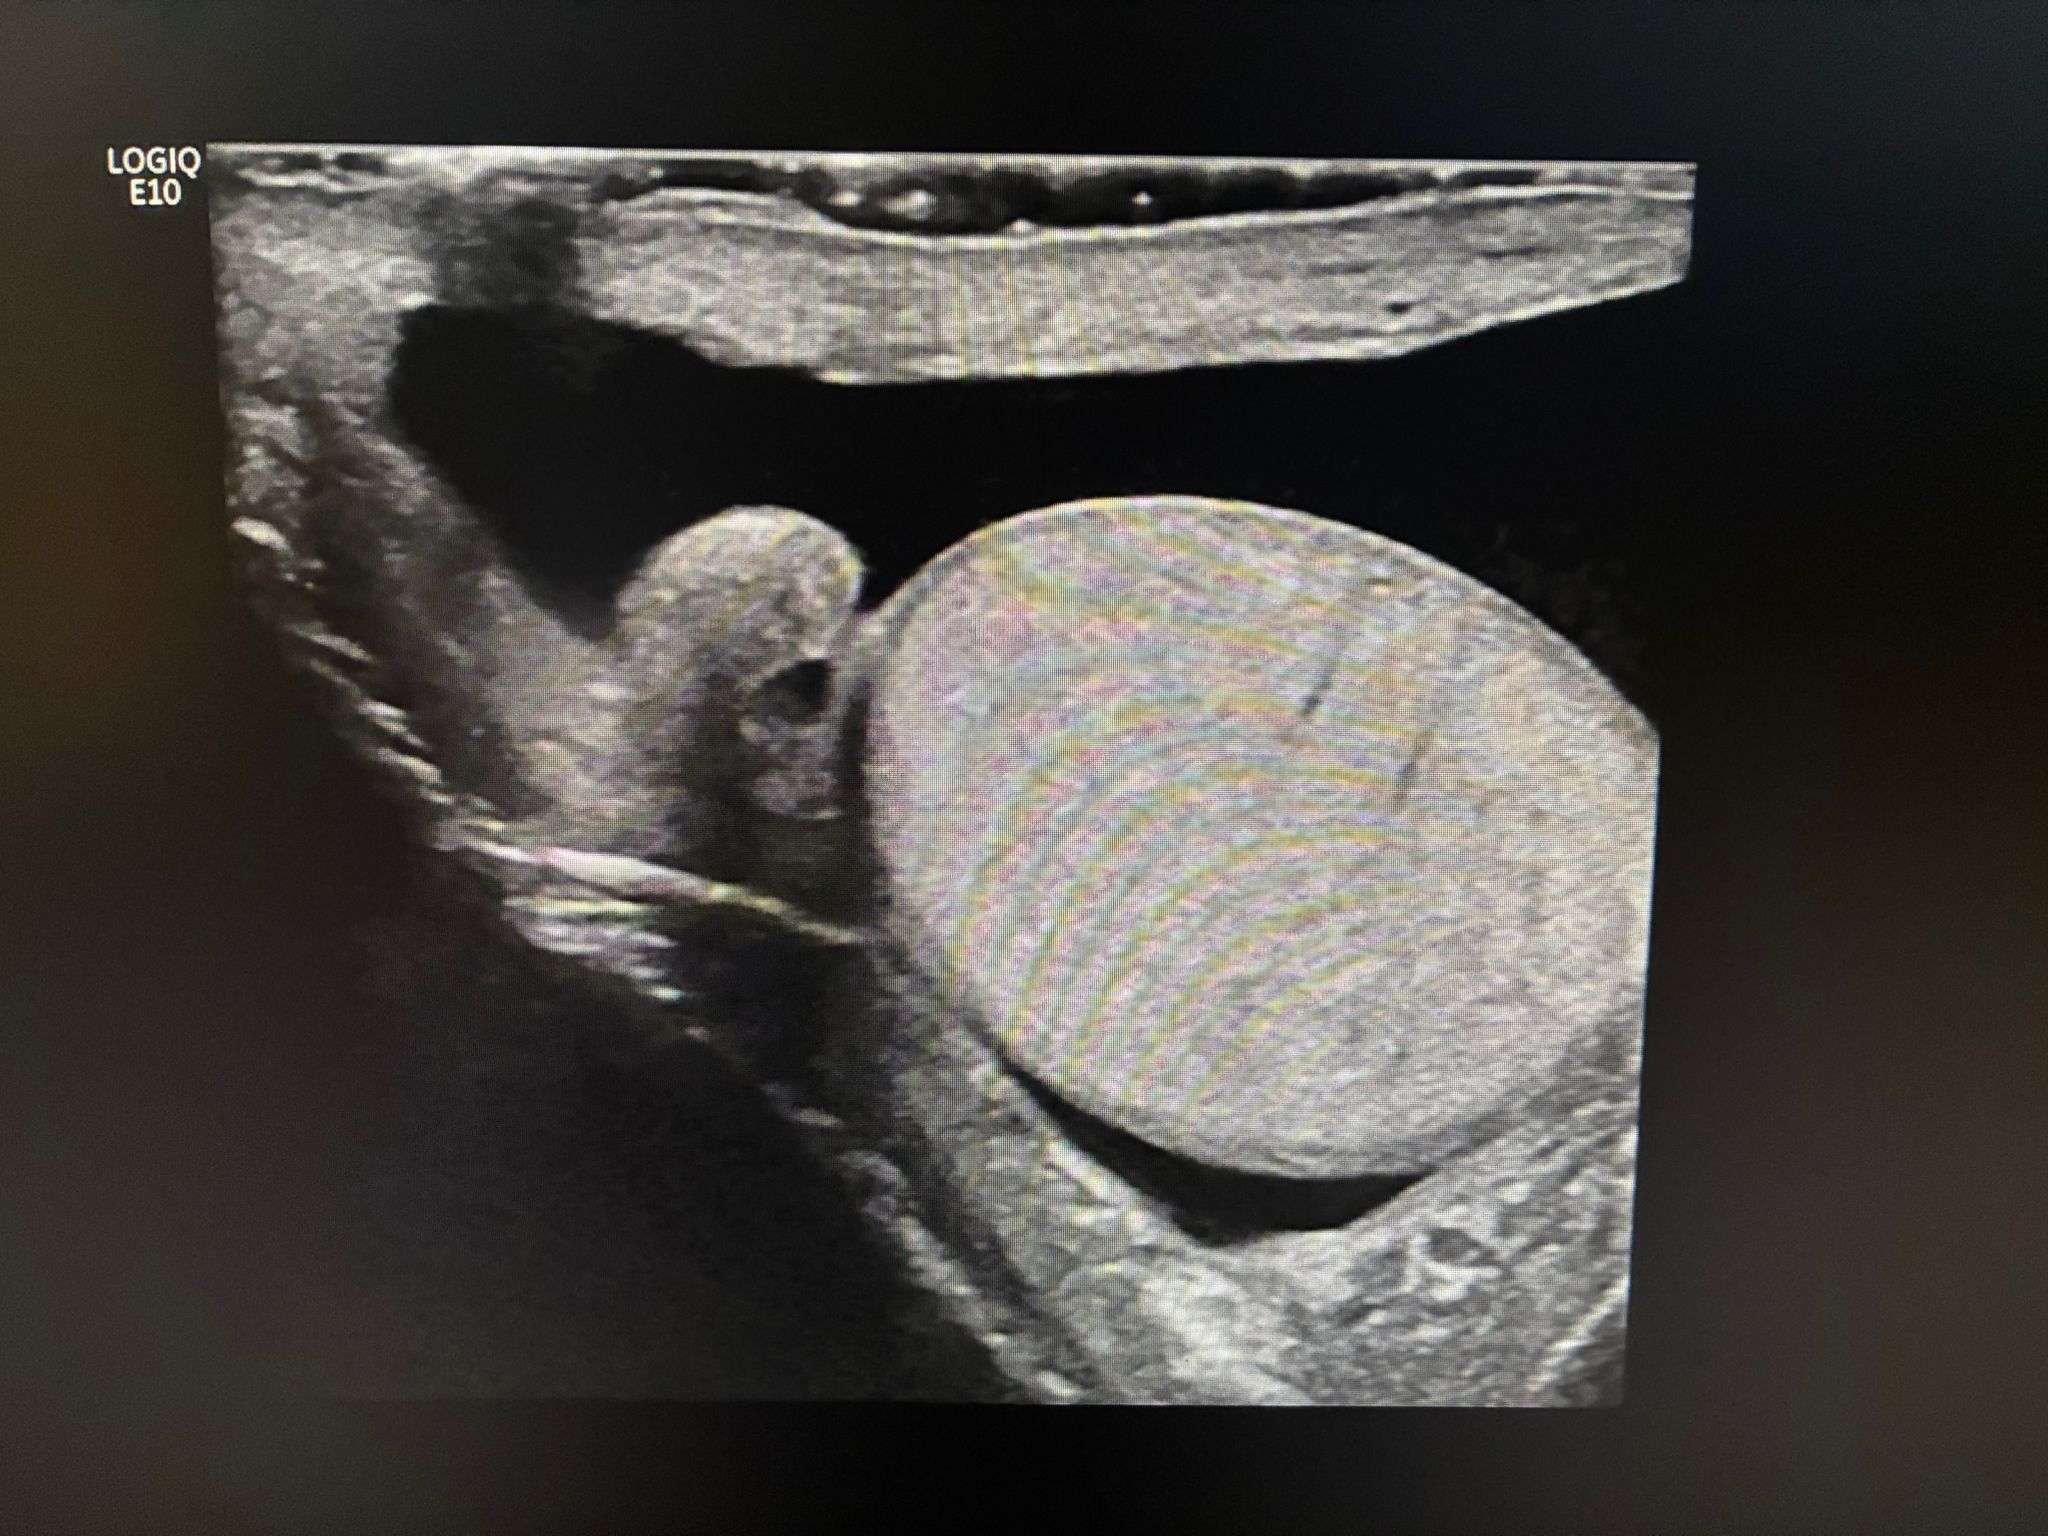

Ecografía a pie de cama: hidrocele multitabicado en bolsa escrotal y teste derecho de menor tamaño en comparación a contralateral.

Ecografía reglada: Hidrocele multitabicado en bolsa escrotal derecha en probable relación con piocele en el contexto clínico. Teste derecho comprimido con discreto aumento de su ecogenicidad. Engrosamiento de cubiertas escrotales derechas. Se observa hiperemia a nivel testicular y epididimario derecho, hallazgos que pueden estar en relación con orquiepididimitis. Teste izquierdo de tamaño y morfología normal.